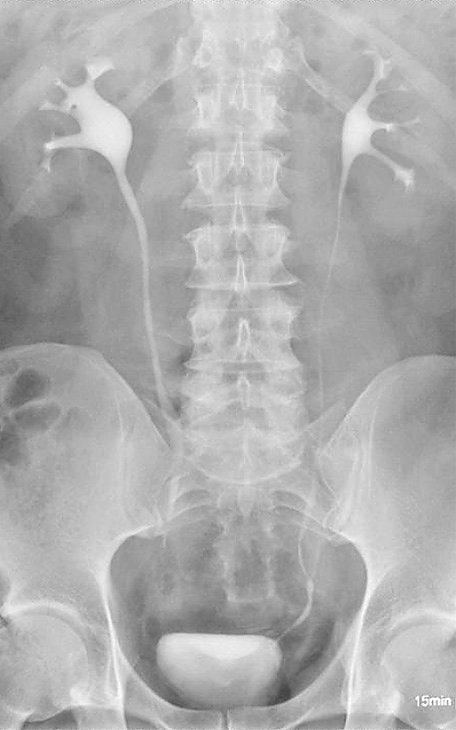

Die Erfindung der Röntgenstrahlen begründete die Radiologie. Heutzutage verwenden wir ausschließlich direkt digitale Röntgensysteme, um eine hohe Qualität der Bilddaten bei gleichzeitig niedriger Röntgendosis zu erlangen. Wir können durch eine spezielle Software auch digitale Ganzbeinaufnahmen durchführen, um so Achsfehler beispielsweise des Kniegelenks nachzuweisen. Auch eine Gesamtaufnahme der Wirbelsäule ist mit dieser sog. Stichingmethode möglich, in Nordthüringen allerdings nur in unserer Abteilung. Für die Beurteilung der Röntgenbilder, die digital gespeichert werden, wird ein automatisches Spracherkennungssystem verwandt. Ein Foschungsschwerpunkt ist die automatische Erkennung von Rundherden (also möglichen Metastasen und Tumoren) beim Röntgen der Lunge. Wir haben drei direkt digitale Röntgensysteme in der Anwendung, von Siemens, Swissray und Samsung. Für die mitunter erforderlichen Aufnahmen von Kranken auf der intensivstation werden zwei fahrbare Röntgeneinheiten genutzt, von Shimadzu und Siemens.